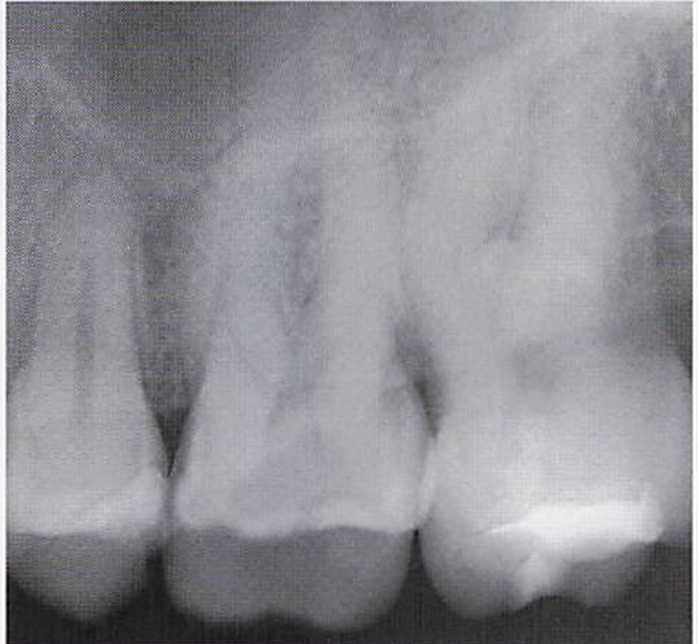

午前-43

32歳の男性。歯ぐきからの出血と排膿が続くようになったことを主訴として来院した。数年前から歯の動揺が気になっていたという。22歳から毎日10本の喫煙をしているが、 全身的な疾患はない。歯周基本治療時の口腔内写真と初診時のエックス親画像を別に示す。 この疾患の特徴はどれか。2つ選べ。

a.栄養障害が原因である。

b.家族内集積が認められる。

c.歯槽骨の破壊が急速である。

d.辺縁歯肉の壊死と潰瘍を認める。

b.c